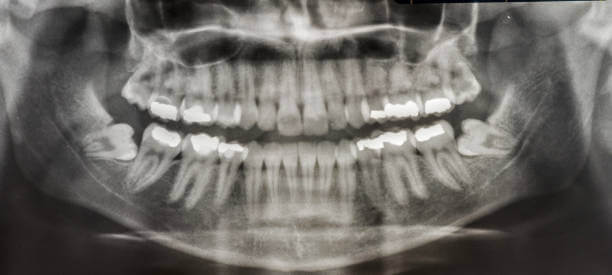

인류의 턱이 작아지면서 입안 깊숙이 사랑니가 자랄 공간이 부족해졌고 이 때문에 사랑니는 눕거나 발치하는 등 썩거나 염증이 생기기 쉬운 모양으로 나오는 경우가 많습니다.

사랑니는 다른 치아에 비해 크기와 모양이 매우 다양합니다. 사랑니는 똑바로 나오지 않고 기울어져 있거나 누워있는 경우 잇몸에 묻혀 있는 부분이 많습니다.